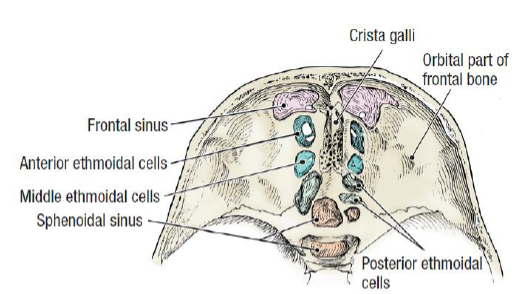

Frontal bone

- Frontal sinus

Ethmoid bone

- Cribriform plate

Sphenoid bone

Foramen rotundum

Foramen ovale

Foramen spinosum

Pterygoid canal

Foramen lacerum (破裂孔)

Optic canal

Sup. orbital fissure

Paranasal sinuses

Frontal sinus

Ethmoid sinus

Sphenoid sinus